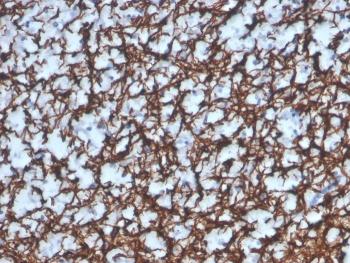

IHC staining of FFPE human brain with recombinant Myelin Basic Protein antibody (clone MBP/4277R). HIER: boil tissue sections in pH 9 10mM Tris with 1mM EDTA for 20 min and allow to cool before testing.

Applications Immunohistochemistry (FFPE) : 1-2ug/ml for 30 min at RT